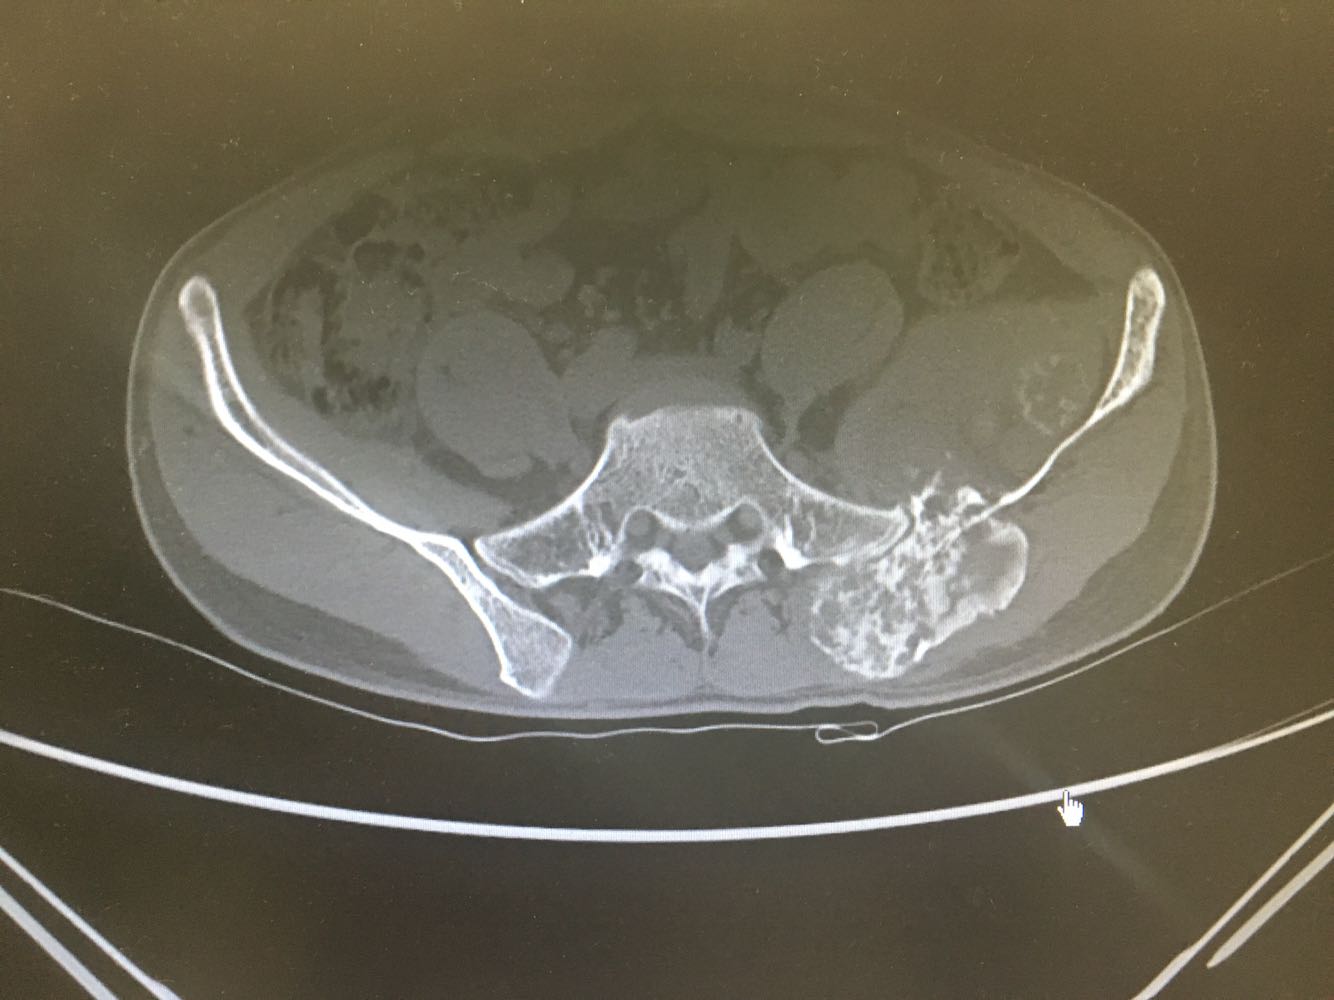

患者,男性,28岁 主诉:左髂疼痛3月 现病史:患者于3月前无明显诱因出现左髂疼痛,行走时加重,休息后缓解,未予重视,1月前发现左腰骶部一质硬肿块,遂至我院门诊就诊,查骨盆X片示:左髂骨骨质改变,现为进一步诊治收治入院,发病以来,神清,精神可,胃纳夜眠可,二便无殊,体重无明显变化。

诊断:髂骨肿瘤(左侧) 治疗:进一步完善相关检查后行活检明确诊断,考虑恶性肿瘤。